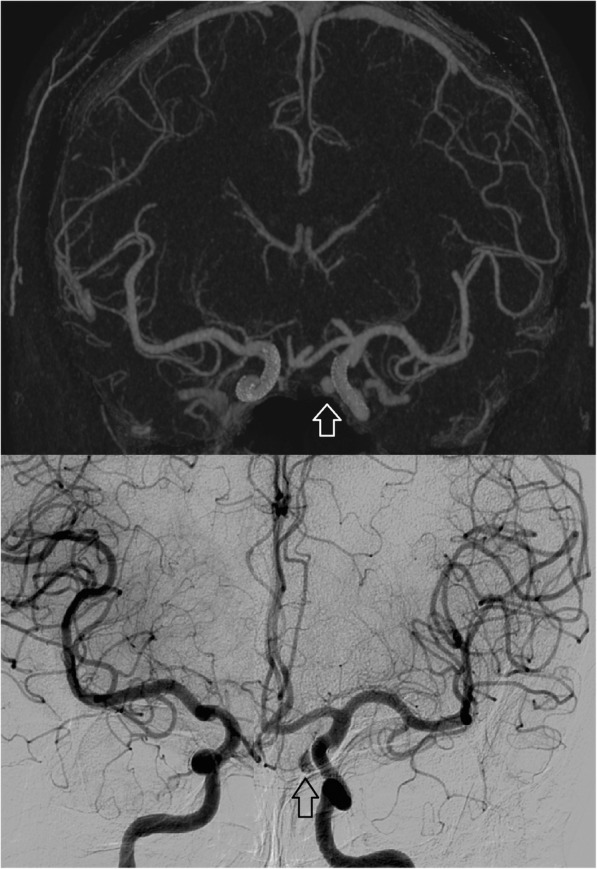

Fig. 3.

Fifty-seven-year-old female with flow diverter placement for treatment of internal carotid artery (ICA) aneurysms on both sides. At follow-up, occlusion of the right ICA aneurysm and residual contrast filling of the left ICA aneurysm (arrows) was seen with full consistency between UHR subtraction CTA (top) and conventional angiography (bottom)